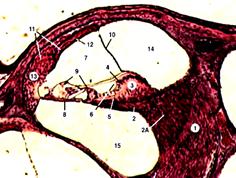

12. Дайте название рисунку и определения структурам, изображённым на рисунке:

|

*С.Л. Кузнецов, Н.Н. Мушкамбаров «Атлас по гистологии, цитологии и эмбриологии» 2- е издание, Москва 2006г. Стр.145